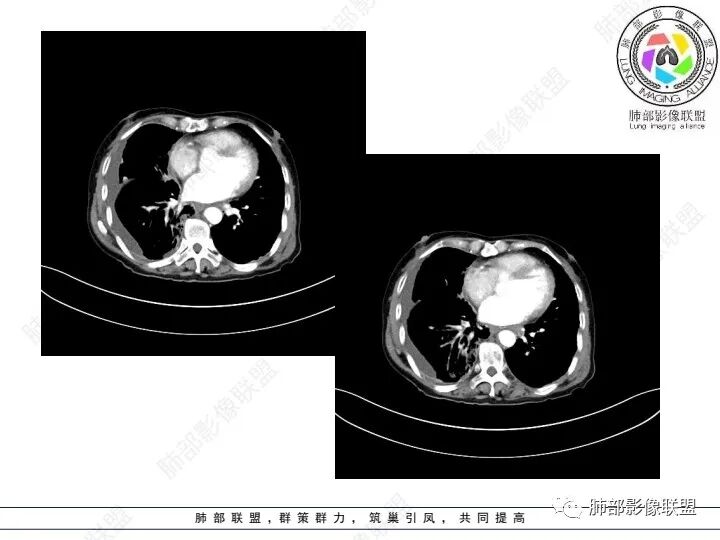

右肺下叶胸膜下不规则肿块,与肺门相连,不均匀强化,胸壁受侵,右肺内多发小结节,下叶血管束增粗,小叶间隔增厚,右肺门及纵膈多发淋肿大淋巴结,融合,右侧胸水,考虑腺癌转移

患者老年女性,腹痛、黑便4小时。查肿瘤结果CA125明显升高,余正常。胸部CT:双肺胸膜下间质性改变,右肺胸膜下多发结节灶,以右肺下叶为大,增强渐进性强化,内低密度灶。右肺门淋巴结肿大伴钙化,右中间支气管狭窄,右侧包裹性胸腔积液。综合考虑恶性,腺癌可能大。鉴别转移。

肺门肿块环形包绕气管,右肺下叶可见一环状强化肿块,右侧胸膜多发强化结节,首先考虑结核并结核性胸膜炎

右肺下叶胸膜下肿块,密度不均,不均匀强化,胸膜栽赃,右肺多发小结节,右肺门及纵膈多发淋肿大淋巴结,下叶支气管受压变窄,右侧胸水,考虑恶性,腺癌转移。

右肺下叶占位,右肺下叶支气管狭窄,周围见软组织密度结节包饶,增强结节病灶强化不明显,右肺胸膜下见多个结节影,考虑恶性病变,低分化腺癌可能

老年女性,以消化道出血入院,右肺下叶靠近脊柱旁肿块,边缘毛糙,有栽赃,内有坏死,胸膜多发结节,右侧胸腔积液,同侧肺门纵隔多发肿大淋巴结,考虑恶性肿瘤可能,不知是一元还是二元,一元消化道肿瘤肺转移?或者二元肺部肿瘤胸膜转移,肿瘤标志物不是很高,考虑间皮瘤?淋巴瘤?

老年女性,右肺门增大见软组织密度影,包绕右肺主支气管腔,管腔明显变窄,并阻塞性肺炎,右侧胸腔及叶间积液,考虑恶性,小 细胞肺癌可能大,鉴别结核

右下肺实变影,周围模糊,均匀强化,内可见低密度坏死,局部胸膜肥厚粘连,胸腔积液,纵隔淋巴结肿大,恶性肿瘤要首先排除。

老年女性,肺气肿背景。腹痛、便血入院。右肺下叶脊柱旁软组织肿块,强化不均匀,中心有坏死,纵隔及双侧肺门多发肿大淋巴结、有融合,右下支气管周围为主,包绕支气管生长,且管壁增厚伴环形钙化、狭窄,增强后有环形强化。右侧胸膜见结节灶,增强后明显强化;右侧胸腔积液。考虑:右下肺恶性肿瘤伴纵隔、肺门多发肿大淋巴结,胸膜转移,低分化腺癌?Ca125明显升高,老年女性 是否有妇科恶性肿瘤?黏液腺癌 肺内、纵隔转移?

老年女性,右下肺实变,胸膜栽赃,淋巴结肿大,散在钙化,考虑恶性,神经内分泌肿瘤可能,鉴别转移瘤

右肺下叶胸膜下病灶,强化不均,右肺门淋巴结肿大,首先考虑恶性,肺原发肺癌可能,另外有胃肠道的症状,转移性不能除外,似乎有胸膜多发结节,胸腔积液呈包裏性,又有肺门区钙化,粘液腺癌转移不除外。

双肺间质性改变,右肺下叶支气管环形增厚,支气管变窄,周围见钙化影,右肺下叶软组织占位,明显的坏死,明显环形强化,两侧肺门及气管隆突下淋巴结肿大。右侧胸腔积液,肝脏周围少量腹腔积液,老年女性患者腹痛便血,Ca125明显增高。考虑1一元论:腹腔恶性肿瘤(胃肠道或卵巢来源)肺内及胸膜腹膜转移;2二元论:右下肺粘液表皮样癌/腺样囊性癌,腹腔胃肠道或卵巢来源肿瘤。

老年女性,肺气肿。腹痛、便血入院。Ca125明显增高。

右肺下叶类圆形软组织密度影,纵隔及肺门多发肿大淋巴结、有融合,右下肺支气管壁增厚伴环形钙化、狭窄,右侧胸膜见结节灶,增强后均匀明显强化;右侧胸腔积液。考虑:右肺下叶肿瘤伴纵隔肺门、胸膜转移,考虑腺癌可能。

突破胸壁,偏右侧多发淋巴结增大,胸膜多发转移,肺气肿背景,首先考虑右肺下叶原发腺癌并多发转移,鉴别腺鳞癌

右肺下叶脊柱旁软组织肿块,外周强化,中心坏死,多发肿大淋巴结,右下支气管周围病灶环绕,密度不均,胸膜下多发结节包裹性胸腔积液。腹部症状。首先考虑结核的可能。。其次腺癌

老年女性,右肺下叶后基底段实性肿块,边缘强化明显,坏死,形态湖泊状,坏死轮廓不清,右肺门下方淋巴结肿大融合,包绕右肺下叶支气管血管束开口,右肺脏层及叶间胸膜多发转移强化结节,右侧胸腔积液,肺气肿背景,支持恶性,肺腺Ca,右肺下叶肿块经皮肺穿刺活检,另消化道岀血,Ca125值明里高,与肠Ca,补充腹部CT平扫及增强和肠镜检查,肠Ca右肺转移待排。

女,69,腹痛、便血4小时。CA125增高。胸部CT:肺气肿背景。右下叶不规则肿块影,处于外周气肿带与正常肺交界区,强化不均匀,中心有坏死;纵隔及肺门多发肿大淋巴结、融合,包绕支气管,部分钙化、环形强化;右下支气管周围管壁增厚伴环形钙化、狭窄。右侧胸膜多发结节灶,增强后明显强化,右侧胸腔积液。考虑恶性,右下肺腺Ca多发转移?转移瘤?鉴别TB、IgG4等。

右下肺肿块,其内坏死边界不清,边缘轻度强化,可见引流支气管,管壁增厚,冰冻肺门,内见斑点状钙化,中间支气管变窄呈针孔样,可见环状强化及血管浸蚀,右侧积液,间隔旁型肺气肿,慢阻肺背景,综和考虑腺并肺门纵隔及胸膜转移,纵隔内淋巴结环状强化,血管破坏显著,肿大淋巴结内多发钙化,引流支气管壁增厚,鉴别一下TB

1、老年男性,腹痛、便血就诊,既往有甲减病史,其余病史无特殊。

2、实验室检查CA125明显升高,其余肿瘤标志物无异常。

3、胸部增强CT示右肺下叶脊柱旁不规则软组织肿块,侵及壁层胸膜外,密度不均匀,不均匀强化,中心低密区可疑坏死,右侧胸腔积液、胸膜结节影或结节样增厚,增强扫描可见强化,右侧肺门及纵隔内可见淋巴结肿大、融合,右侧中尖段支气管及右肺下叶支气管受侵,管腔狭窄。

4、综上,老年男性,CA125升高,右肺下叶肿块侵犯胸壁,伴纵隔、右肺门及纵隔淋巴结肿大,右侧胸腔积液、胸膜增厚伴结节影,强化明显,应该为一较典型的肺癌伴肺胸膜腔及肺门纵隔淋巴结转移,尤其是肺腺癌。